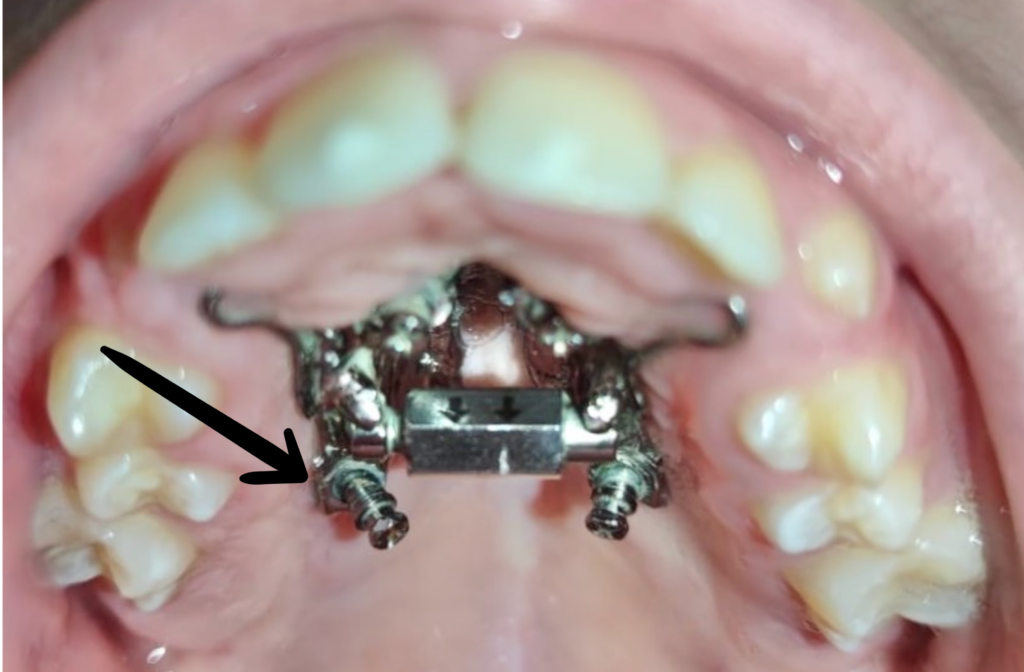

9. Microcargol afluixat, amb moviment o inflamació

En els tractaments amb aparells amb suport ossi, els cargols poden perdre força degut a restes de menjar que provoquen inflamació.

Si es dóna el cas, realitzeu els passos següents:

1. Contacteu amb la clínica Boca a Boca i agafeu hora amb la Dra. Villa. Els cargols són un tema quirúrgic i la Dra. Cubells no us pot ajudar en aquest sentit.

2. Higiene molt exhaustiva de la zona, especialment amb el fil dental i/o els raspallets interdentals. (Podeu mullar el fil o el raspallet amb clorhexidina).* Instruccions d’higiene

3. Apliqueu Gel de clorhexidina la llaga, després de cada raspallat i a demanda entre raspallats si cal.* (Producte complementari a les instruccions d’higiene; ells sols NO solucionaran la inflamació).

Microcargol anclat

Microcargol afluixat